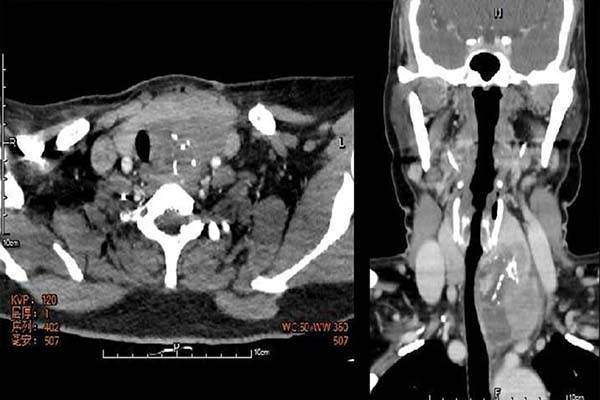

张女士在当地体检时发现左侧甲状腺结节,并未重视;随后的6个月,她的脖子快速增粗,超声检查提示左侧甲状腺肿物,大小约5cm,考虑未分化癌可能性大。在前往第一医院南院甲状腺外二科就诊后,张华第一时间邀请超声科、CT/放射线科、病理科、内分泌科等相关科室专家,启动多学科(MDT)会诊。专家团队通过颈部及胸部影像检查结果发现,患者左叶甲状腺肿物达4.8cm×5.0cm,伴随多发淋巴结肿大,左侧侧颈区淋巴结疑似转移,但暂未发现远处转移征象。经综合判定,患者仍具备手术机会,可实施双侧甲状腺全部切除+左侧中央区淋巴结清扫+左侧侧区淋巴结清扫术。